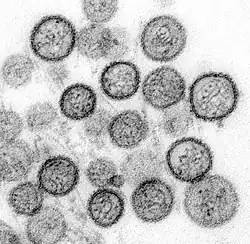

- Influenza viruses